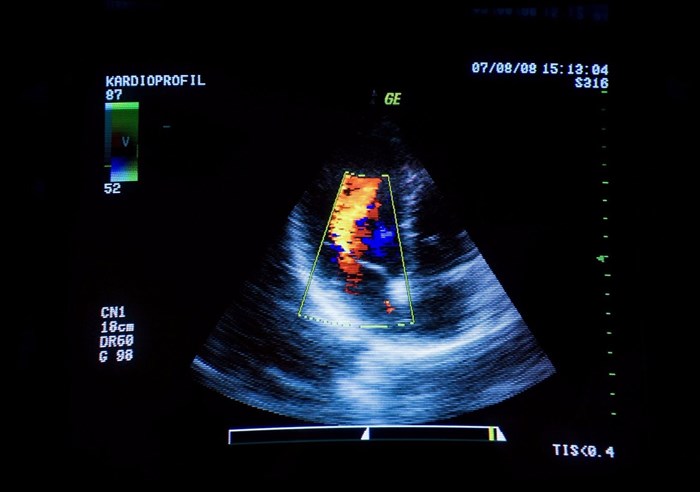

An example of a Doppler ultrasound is an echocardiogram (ECG) which is useful for creating images of the cardiovascular system (showing the state of cardiac valves, possible heart abnormalities, blood leakage, or valvular regurgitation), as well as determining cardiac tissue movement in specific areas.

Ultrasound scan of a person's heart, visualised on a computer screen.